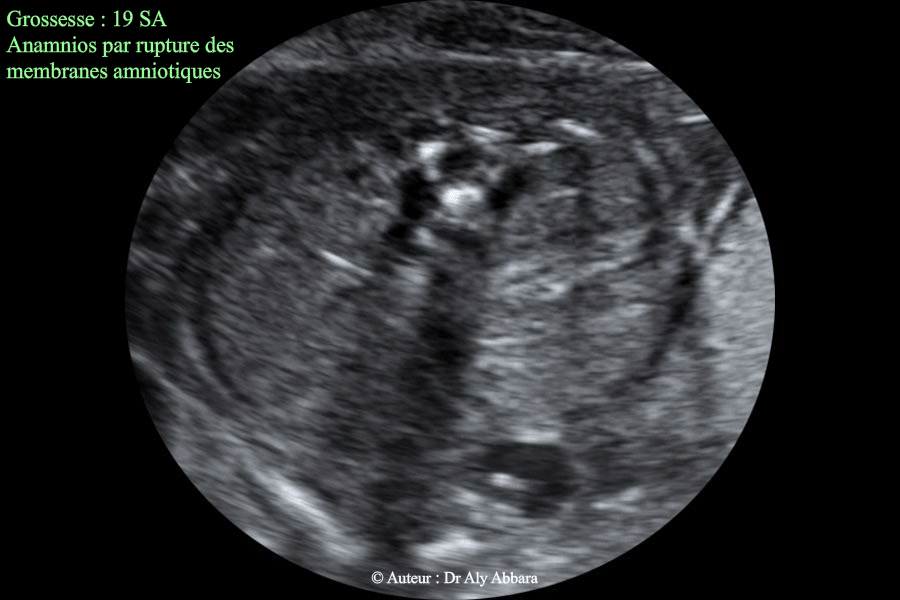

Anamnios en rapport avec une rupture prématurée des membranes à 19 SA - Reins identifiables

Images échographiques montrant un anamnios à 19 SA ; conséquence d'une rupture prématurée des membranes survenant 36 heures auparavant.

L'image échographique montre l'absence totale de liquide amniotique avec la mise en évidence de deux reins normaux permettant d'éliminer la présence d'une pathologie rénale bilatérale pouvant donner échographiquement les mêmes images (exemple : agénésie rénale bilatérale).

Les autres images échographiques montrent également, dans le présent cas : le repli du rachis fœtal ; le repli du placenta et la vessie bien individualisable.